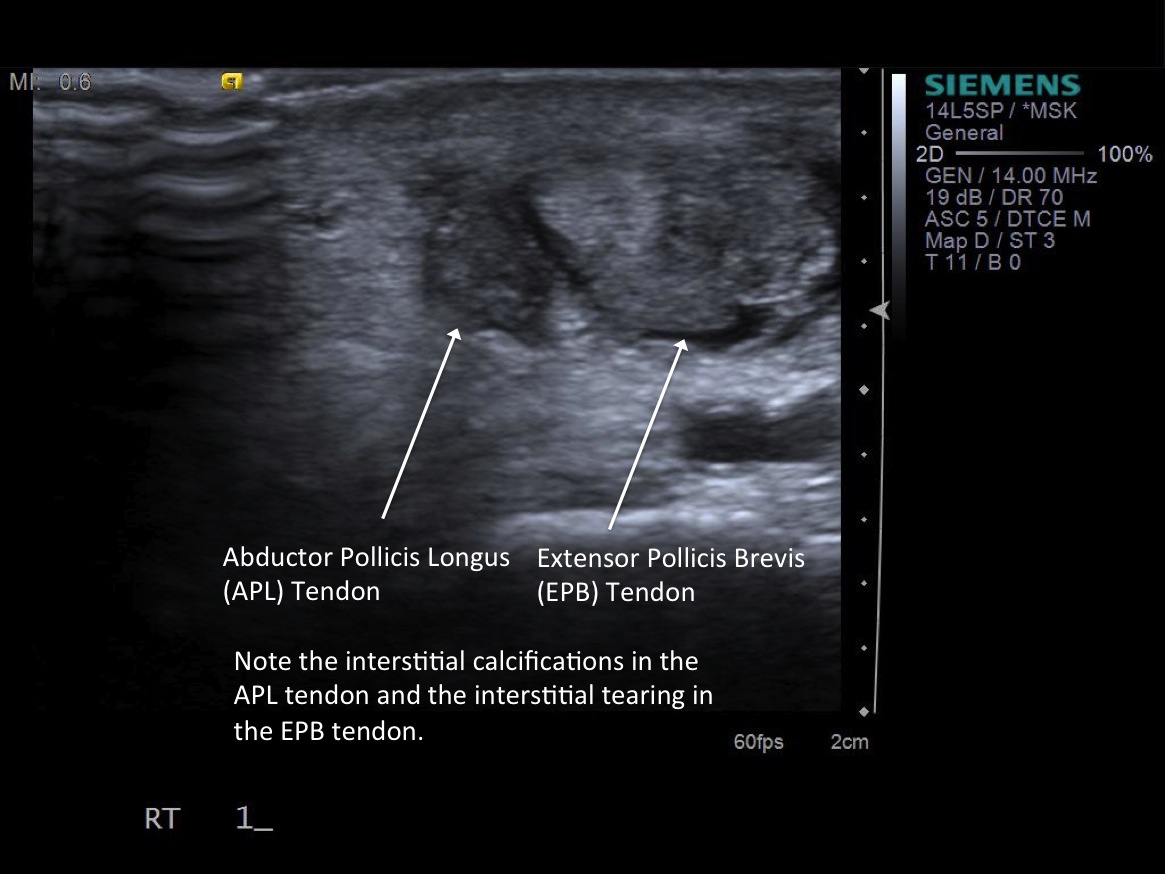

• probe: 14Mhz hockey stick probe

3. Place probe in short axis over first comparment extensor tendons-- Extensor pollicis brevis and abductor pollicis longus. description description

6. Inject 1% lidocaine superficially with 25g 1.5” needle. Advance needle deeper surface of the 1st extensor tendon sheath. Oftentimes, the APL and EPB tendons are in separate sheaths and may require separate injections. Then, unscrew syringe from needle for greater needle control.

7. Under ultrasound guidance,advance needle into the 1st extensor tendon sheath. In this case the APL and EPB have separate sheaths and require their own injections. Test inject with 1% lidocaine. If no resistance, switch 1% lidocaine for injectable steroid mixture. If there is resistance, reposition needle and test inject again. Inject 1 cc of injectable steroid/anesthetic mixture.